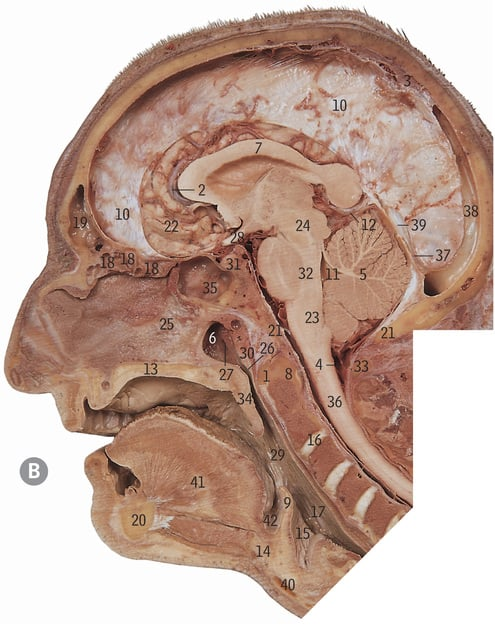

24

Midbrain

32

Pons

23

Medulla oblongata

4

Clivus

What does the brainstem lie on in the occipital bone

5

Cerebellum

17

Inferior colliculus

Cerebral aqueduct

2

Cisterna magna